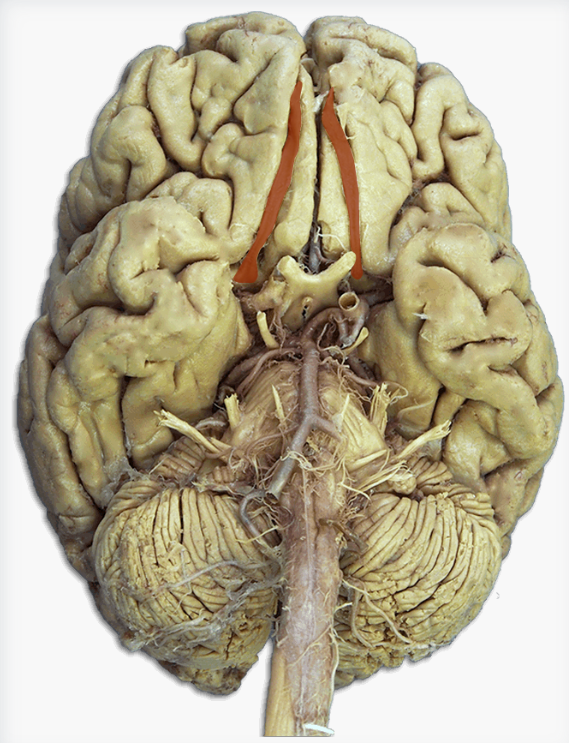

What is this?

Anterior cerebral artery

Label this cranial nerve

Olfactory (CN I) nerve

Label this cranial nerve

Optic (CN II) nerve

Label this cranial nerve

Oculomotor (CN III) nerve

Label this cranial nerve

Trochlear (CN IV) nerve

Label this cranial nerve

Trigeminal (CN V) nerve

Label this cranial nerve

Abducens (CN VI) nerve

Label this cranial nerve

Facial (CN VII) nerve

Label this cranial nerve

Vestibulocochlear (VIII) nerve

Label this cranial nerve

Glossopharyngeal (CN IX) nerve

Label this cranial nerve

Vagus (CN X) nerve

Label this cranial nerve

Accessory (CN XI) nerve

Label this cranial nerve

Hypoglossal (CN XII) nerve